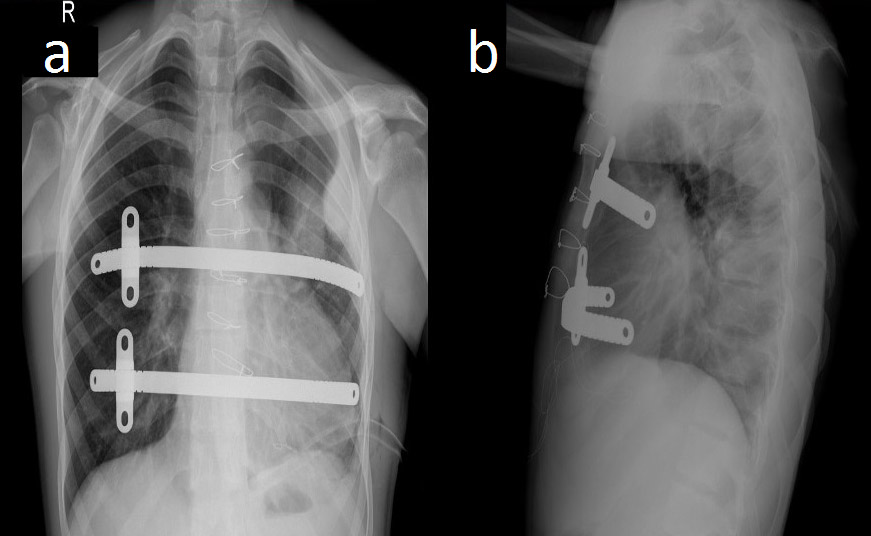

Figure 2. Postoperative chest radiographs showing the bar positions in anteroposterior (a) and lateral (b) projections.

The authors decided to perform synchronous ASD closure and correction of the pectus excavatum deformity. The patient was placed in the supine position with the arms abducted to expose the anterior and lateral chest wall. The deepest point and the bilateral highest points (thoracic entry and exit points) of the thorax were marked. Two bars were used to correct the deformity. In total, four skin incisions were made: in the third intercostal space on the left side, in the fourth intercostal space in the anterior axillary line, in the third intercostal space on the right side, and the fourth intercostal space in the anterior axillary line on the right side. Subcutaneous pockets (two left and two right) were made by blunt dissection, and a median sternotomy was performed. The introducer was slowly advanced across the anterior mediastinal space immediately under the sternotomy. Using the introducer, a strand of cloth tape was pulled through the tunnel. The tape functioned as a guide for placement of the pectus bars, and then the pericardium was opened. The patient was put on cardiopulmonary bypass, the superior and inferior vena cavae were clamped, and the aorta was clamped. Cardioplegia was administered. The ASD was closed with a pericardial patch and cardiopulmonary bypass was terminated. Sternal wires were placed for sternal closure, but were not twisted. The introducers were linked to the tape and two bars were inserted with the convexity facing posteriorly, and the sternal wires were twisted. A bar flipper was used to turn the two bars over while pulling up the sternum. The rotated bars were fixed with butterfly stabilization on the right sides of the chest, and were fixed with PDS sutures on the left side (Figure 2). There was no need to use a thoracoscope, because the authors were able to see the procedure under direct vision through the sternotomy. The incisions were closed and the patient was taken to the cardiac intensive care unit with a mediastinal and two thoracic (left and right) chest tubes.